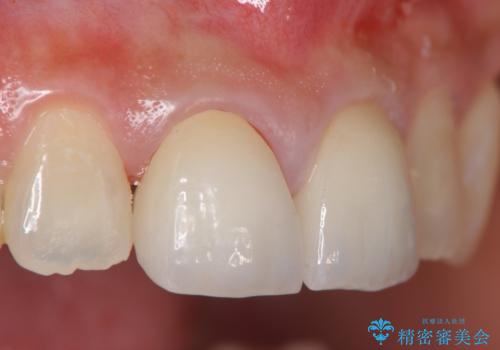

- 44万円(仮歯・ジルコニアクラウン×4)費用は治療当時の料金となります

金属を用いないジルコニアセラミッククラウンは透明感の再現性に優れ、審美性と自然な仕上がりの両立を期待することができます。